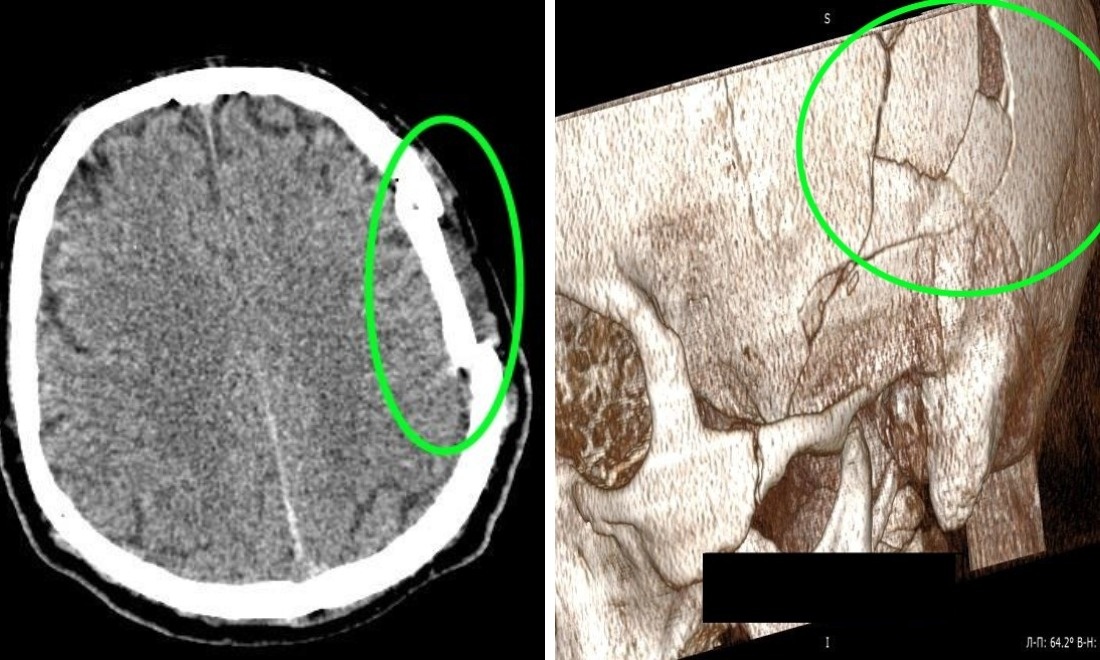

Успешную операцию провели специалисты больницы № 34 в Новосибирске. Врачи восстановили целостность черепа и соотношение костей, сохранив собственные ткани пациента. Об этом сообщили в региональном Минздраве. Мужчина получил тяжёлую черепно-мозговую травму на рабочем месте, когда на него упала коробка передач грузовика. Вес этой детали превышает 200 килограммов. В результате удара у пострадавшего произошло смещение костных фрагментов и сдавление головного мозга. Главный врач Ярослав Фролов отметил, что благодаря современному оборудованию больницы удалось провести операцию без использования имплантов и внешних вставок. Подобные операции часто необходимы при тяжёлых травмах головы. Оснащение операционных в больнице позволяет проводить такие вмешательства, что значительно повышает шансы на успешное восстановление пациентов.

Мужчина получил тяжёлую черепно-мозговую травму на рабочем месте, когда на него упала коробка передач грузовика. Вес этой детали превышает 200 килограммов. В результате удара у пострадавшего произошло смещение костных фрагментов и сдавление головного мозга.

Главный врач Ярослав Фролов отметил, что благодаря современному оборудованию больницы удалось провести операцию без использования имплантов и внешних вставок.